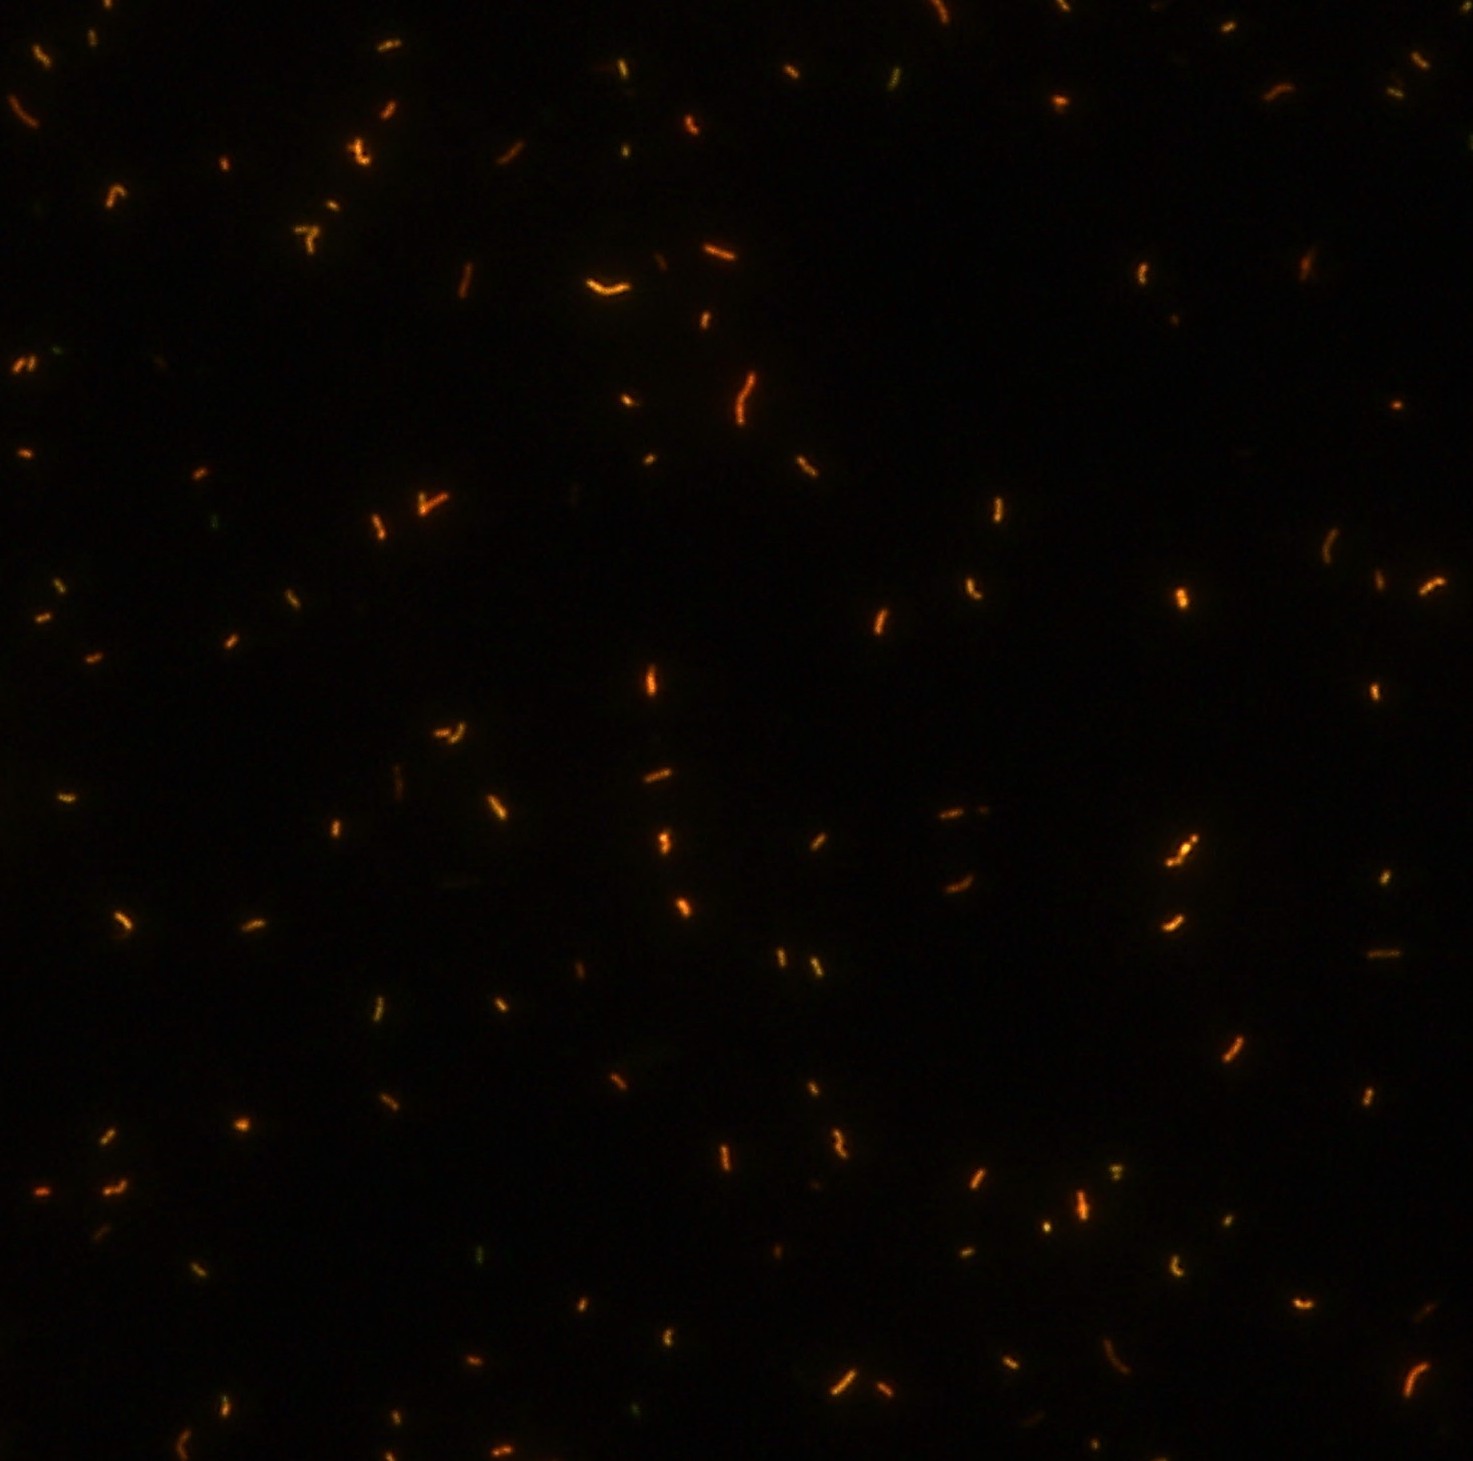

顯微染色技術(shù)是檢測結(jié)核桿菌方法之一。分枝桿菌細(xì)胞壁中含有分枝菌酸,其可以與染料牢固結(jié)合,具有“抗酸性”的特征。熒光染料金胺-羅丹明在染色中與抗酸生物細(xì)胞壁內(nèi)的分菌酸相結(jié)合,并耐受酸醇(脫色劑)清洗脫色。反染色劑高錳酸鉀被用來顯出染色生物。AFB(熒光)染色試劑盒設(shè)計(jì)既可用于染色機(jī),也可用于手工染色。產(chǎn)品穩(wěn)定性好,染色效果佳。

染色結(jié)果 熒光法×400

用于分枝桿菌、諾卡菌等細(xì)菌抗酸染色,包括熒光染色。